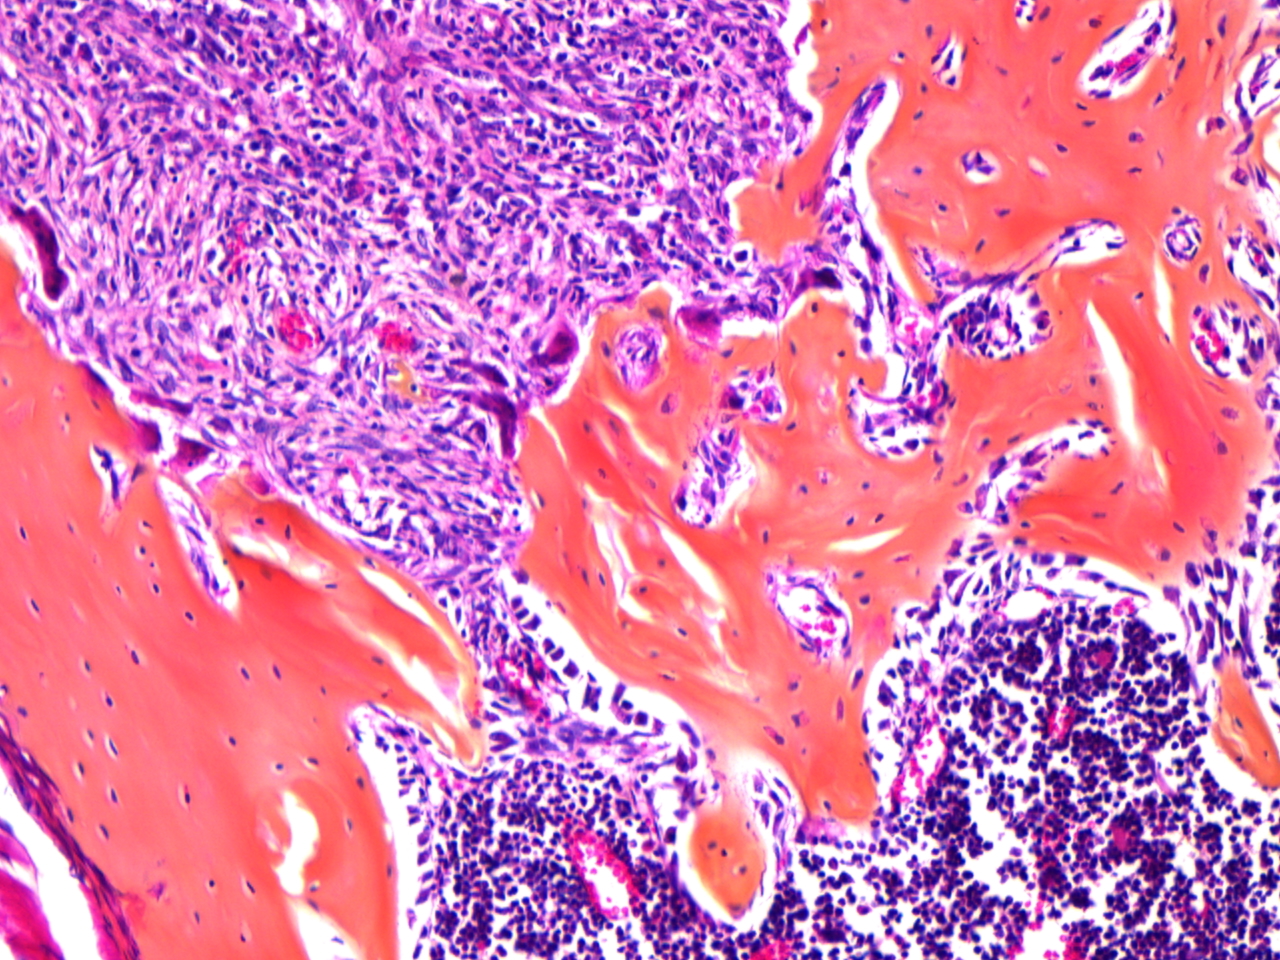

The MD Anderson Bone Histomorphometry Core Laboratory provides histomorphometric analyses of non-decalcified bone specimens. Bone specimens are processed for histology and can be stained for static and dynamic histomorphometric analyses (Osteomeasure or the Bioquant Osteo II system). The core can provides slides, data, training

Research Histology Core Lab: Bone Processing, Embedding and Sectioning

Bone Histomorphometry Core: Staining and Analysis